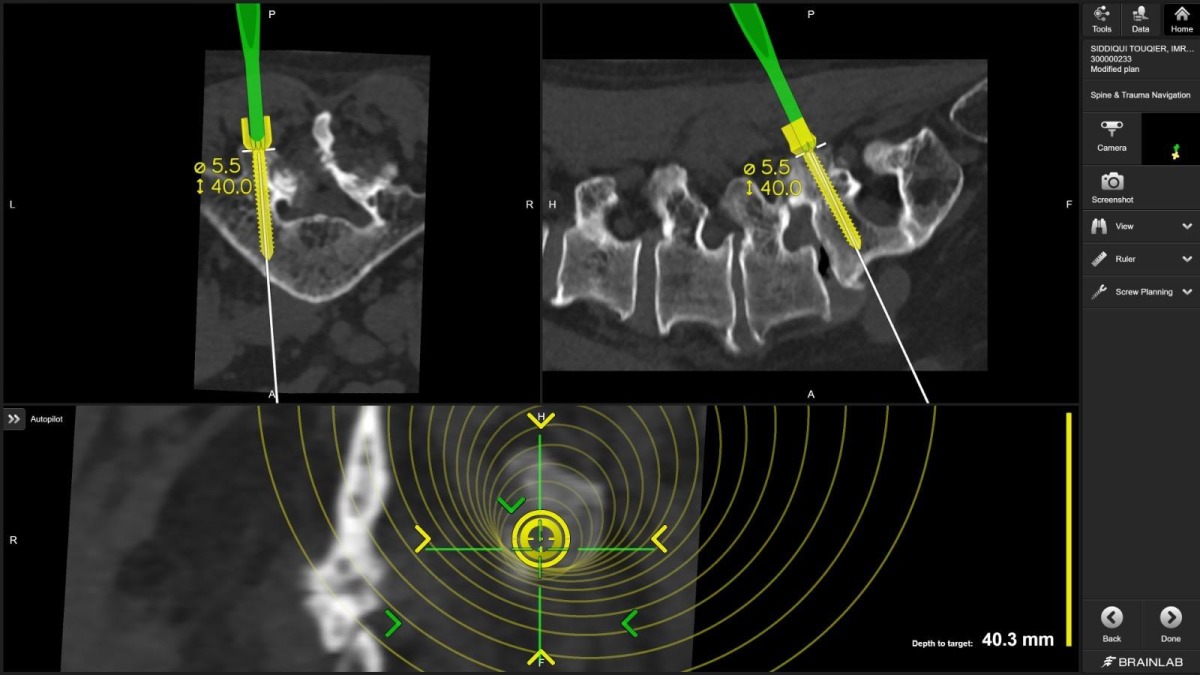

"For the first time in Qatar, I used virtual reality technology to plan spine screws before surgery," Dr. Belkhair explains. "These electronic glasses showed me 3D images of the patient's CT scan, allowing me to plan screw placement in the perfect position. What I saw in those glasses translated directly into the operating room, visible on screens, guiding every movement."

Navigated spine surgery combines real-time, three-dimensional imaging with optical or electromagnetic tracking systems that follow surgical instruments as they move through the body. Think of it as GPS for the human spine, mapping instruments within the vertebral anatomy with millimeter-level accuracy.

Dr. Belkhair took this further. Before the patient entered the operating room, he used virtual reality glasses that transformed CT scan data into an immersive, three-dimensional surgical rehearsal space. He could rotate the spine, zoom into pedicles (the narrow bone corridors where screws must pass), measure angles, and plan screw trajectories with unprecedented detail.

"The planning became the roadmap. The navigation ensured we followed it perfectly," he notes.

Dr. Belkhair's integration of VR planning with intraoperative navigation creates a seamless workflow: plan in virtual space, execute with real-time guidance, verify with immediate imaging.

"The glasses showed me the patient's spine as if I could hold it in my hands," Dr. Belkhair describes. "I could see where every screw needed to go, what angle, what depth. It's surgical precision at a level we couldn't achieve even five years ago."